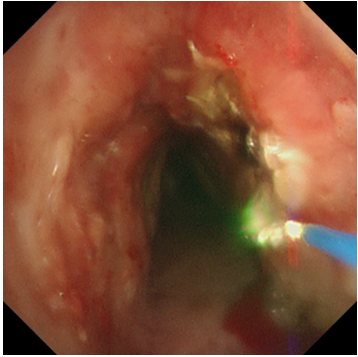

冷凍修復(fù),深度“清創(chuàng)”:隨后,應(yīng)用冷凍探頭對殘余的增生組織及基底進行凍融治療。極低溫的探頭接觸組織,能使其變性、壞死并最終脫落,同時還能有效止血、減少瘢痕形成。這一步驟如同為氣道進行一次深度的“保養(yǎng)與清潔”,能更徹底地清除病灶,降低復(fù)發(fā)風(fēng)險。

兩種技術(shù)優(yōu)勢互補,相得益彰,在微小創(chuàng)傷的前提下,實現(xiàn)了對復(fù)雜氣道狹窄的最大化疏通。